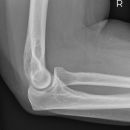

Ellenbogen seitlich (2. Ebene radio-ulnar)

Beurteilungskriterien

- Weichteilzeichen: Verlagerung des ventralen (proximal der Fossa coronoidea bis 5mm breit ist normal) und dorsalen distalen Humerusfettkörpers (normalerweise nicht sichtbar), Supinatorfettlinie: normalerweise etwa 3-4cm lang und 2-3mm breit, parallel zum proximalen Radius

- Target areas: vordere und hintere Humeruskontur, Radiusköpfchen, Processus coronoideus (evtl. zusätzlich 45°-Schrägaufnahme), Olecranon, harmonische Darstellung des Radiusköpfchen? Impressionen? Stufe? Verdichtungen, Fissur? Knickbildung?

- Auftreten, Verschmelzung und Lokalisation der Epiphysenkerne -> Verlagerung? vgl. Anatomie Kids! Viele kindliche Verletzungen sind anhand der Verlagerung der Knochenkerne differenzierbar! Evtl. Vergleich mit Gegenseite oder MRT hilfreich.

- Täuschungsmöglichkeiten: Persistierende Apophysen an Olecranonspitze oder Processus coronoideus, Kortikaliseinkerbungen als Residuen der Epiphysenfugen (v.a. des Olecranons)

- Kids: Kreuzung vordere Humeruslinie mit Radiushalsachse im mittleren Capitulumdrittel? Abweichung -> dislozierte, supracondyläre Humerusfraktur? Epiphysenfugenverletzung? Dislokation des proximalen Radius? Luxation?

Cave:

- 50% der Radiusköpfchenfraktur sind nicht disloziert und u.U. nicht nachweisbar -> bei klinischem Verdacht ist ein positives Fettpolsterzeichen nahezu beweisend! Greenspan-Aufnahme, evtl. CT oder MRT!

- Distale Humerusfraktur (Trochlea oder Capitulum) mit frontaler Bruchebene -> "Halbmondzeichen" durch plankonvexe(s) und in die Fossa cubiti dislozierte(s) Fragment(e) -> CT zur Beurteilung der Gelenkflächenverhältnisse.

- Komplexe Frakturen, Gelenkflächenverhältnisse? -> CT